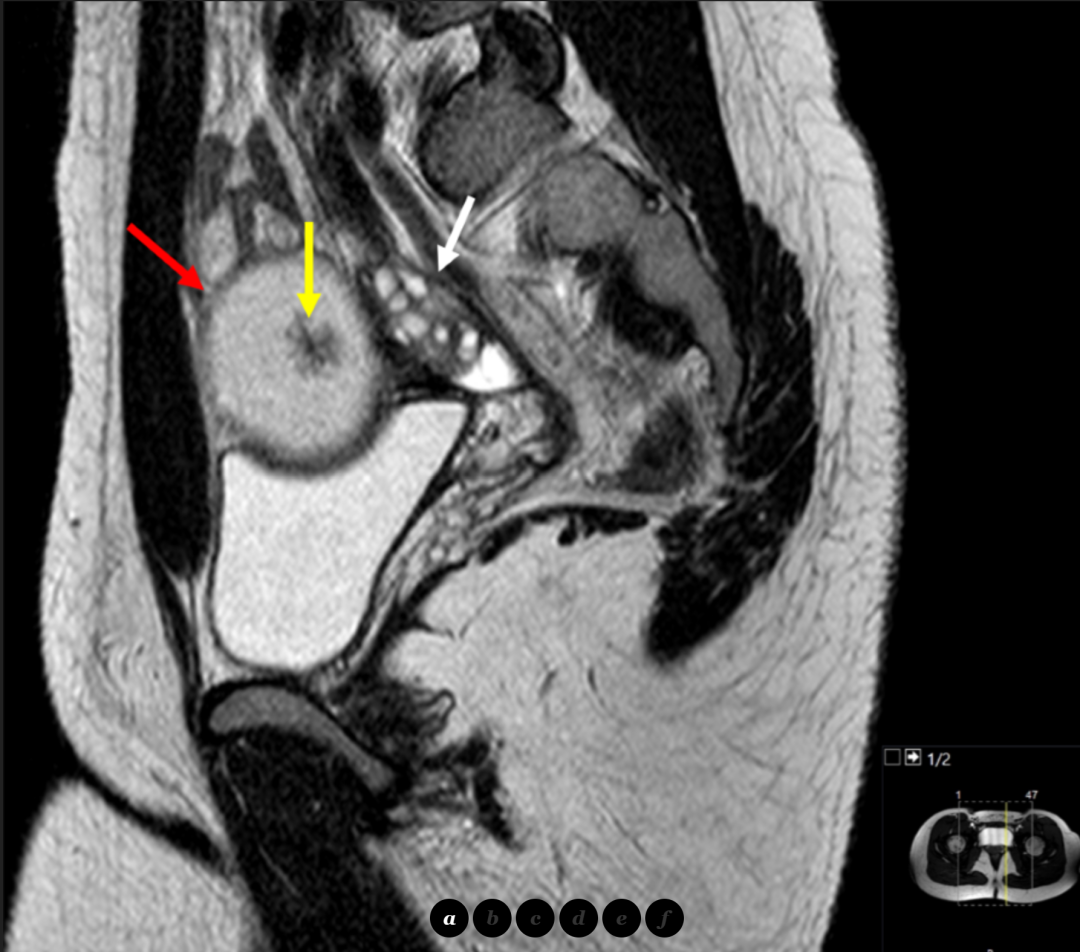

卵巢交界性粘液性囊腺瘤是一种具有潜在恶性的卵巢肿瘤,占卵巢肿瘤的10%~20%,常见于绝经前女性病因目前尚不明确,但年龄家族史未生育长期使用雌激素替代疗法等因素可能增加发病风险症状早期多无明显症状,通常在体检或因其他妇科问题行超声检查时偶然发现当肿瘤较大时,可能出现腹胀腹部。